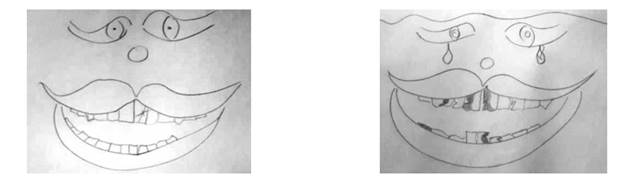

Los dibujos realizados bajo la supervisión de educadores, sin presencia de integrantes del equipo investigador, dieron éstos resultados. En el análisis de los dibujos se tomaron como referencia trabajos de Paul Ekman y Freitas- Magalhaes en cuanto a la interpretación de la sonrisa como lenguaje corporal que muestra “el alma interior” 32-33. Se distinguen tres grupos acerca de las imágenes: el primero con sonrisas de colores vivos en rojo, rosado o hasta con tintes de amarillo, mostrando bocas alegres, abiertas, con presencia de dientes, incluso acompañada por flores como rosas.

Otro grupo mostró sonrisas más pequeñas, tristes, grises (en blanco y negro).

El tercer grupo también en blanco y negro con alguna tonalidad de rojo y verde. Se aprecian sonrisas con ojos, narices, corazones, elefantes, piernas, flores y lágrimas en el rostro cuando la boca está deteriorada.

Los dibujos de bocas con alteraciones expresan ausencias dentarias, caries representadas por manchas oscuras, pigmentaciones dentarias en color amarillo, labios agrietados (figs 1,2,3).